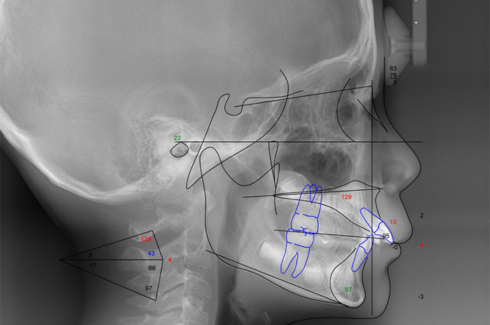

採得したデジタルデータを、コンピュータ解析します(セファロ分析および治療シミュレーション)。 また上下顎骨の前後的および垂直的バランスを評価し、今後の成長を考慮した上で治療方針を決定します。 サリバテストでは、口腔内の細菌と唾液の性質を評価し、現在の口腔内環境に合わせた虫歯予防プランを作成します。 検査結果を元に十分な相談の上、できる限り希望に沿えるよう適切な治療の計画を立てます。

セファロ分析

頭部X線規格写真